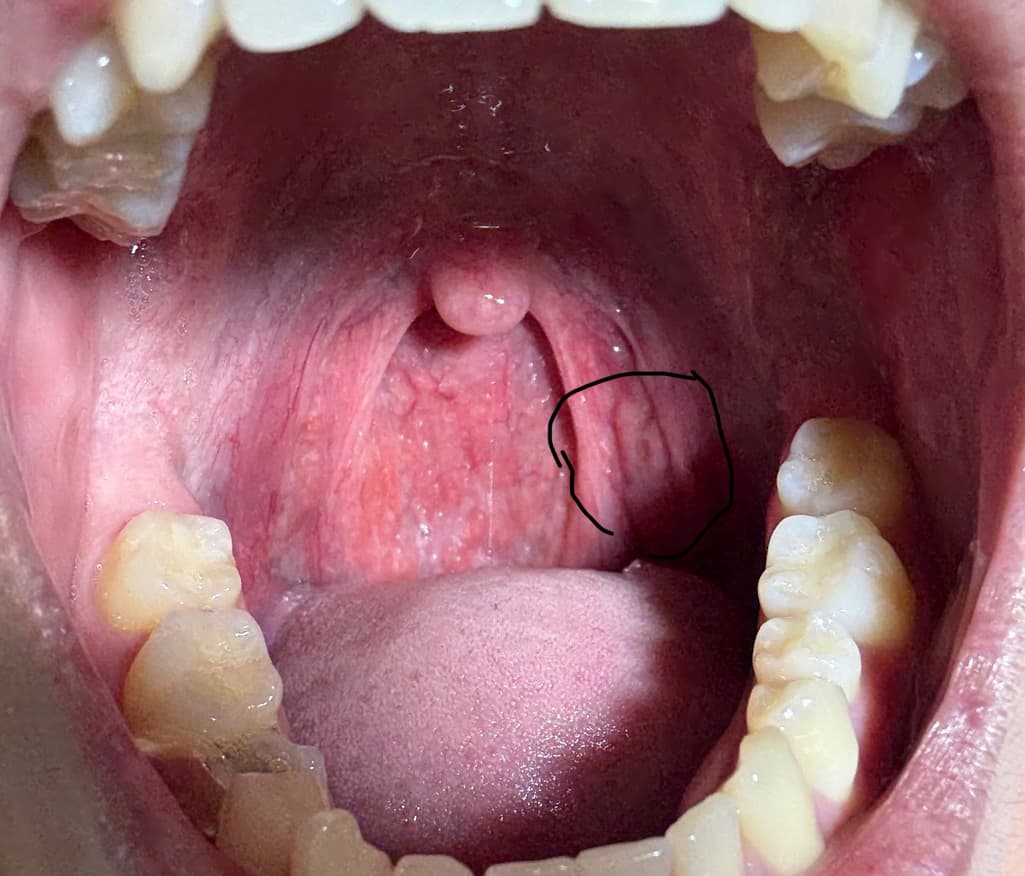

사진상 우측 편도부분 편도암 의심가는지 확인가능할까요

평소 편도가 자주 부어있고 편도염도 잦긴합니다. 하지만 사진상 우측에 있는 편도 부분이 비대칭처럼 육안상 부어있습니다.그리고 작은 여드름처럼 뭔가 있습니다.과거에는 이런적 없었고 비대칭처럼 된지 몇개월 지났습니다. 딱히 커지는지는 모르겠습니다만, 편도암 의심가는 양상일까요? 과거 이비인후과 내원했을때는 대충 보시더니 별거 아니라고 하셨습니다만, 문제있으면 다시 내원하려고합니다.

사진상 편도선으로 의심되는 부위의 점막의 불규칙한 표면 변화가 관찰되지만 편도암에서 관찰되는 종괴나 궤양성 병변이 아니므로 편도암으로 보기는 어렵습니다. 평소 편도염의 재발로 인한 만성 편도염이 발생하였고 이로 인한 편도 점막의 변화로 판단됩니다. 크기나 모양의 변화가 없다면 좀 더 지켜보아도 되겠으며 육안 소견상 편도암이 의심되는 것은 아니므로 당장 추가 검사나 진료를 필요하지 않겠습니다.